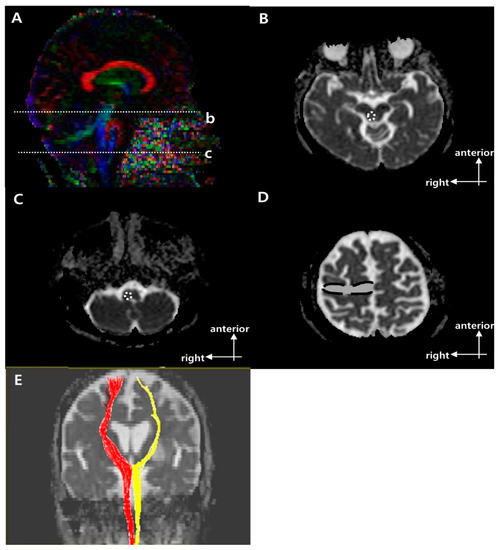

2.3. Fiber Bundle Tracking